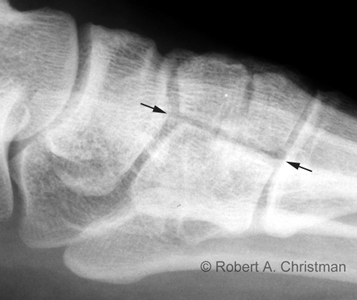

Lateral view

• Critique

• superimposition of metatarsals

• visualization of talocalcaneal joint

• dorsal displacement of the proximal base of the 1st or 2nd metatarsal

• seen on lateral view